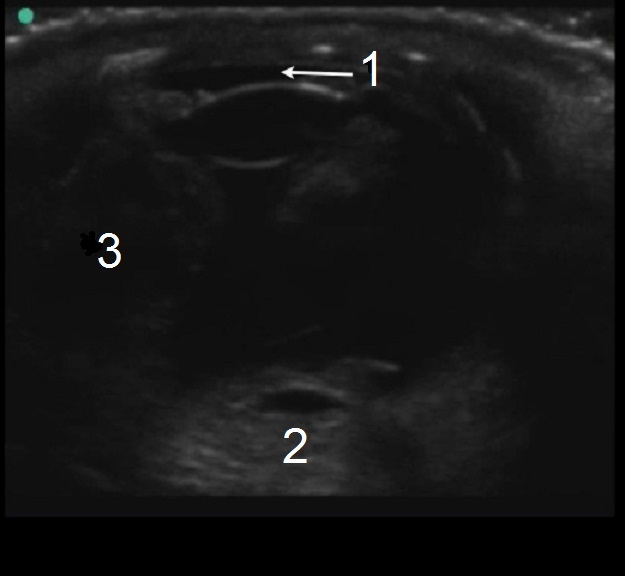

Ocular Ruptured Globe 2 Image

平坦な前房

球形の損失

硝子体出血